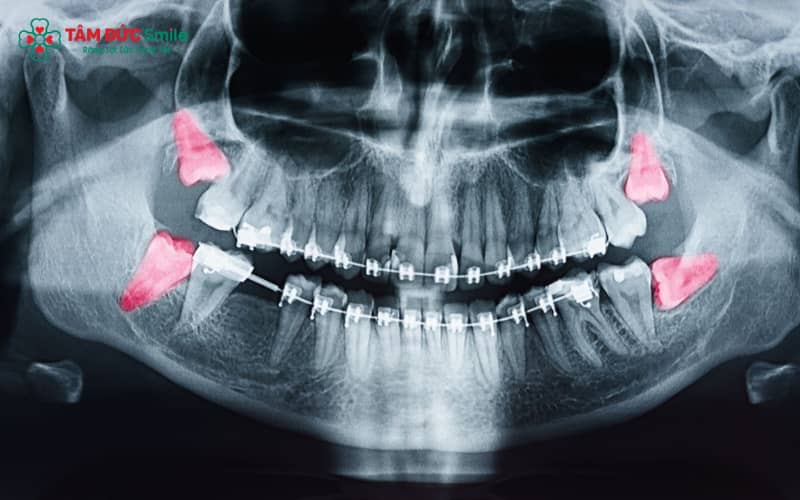

5.2 Do mầm răng không phát triển hoặc tiêu biến

Có nhiều người khi chụp X-quang nha khoa cho thấy mầm răng số 8 hoàn toàn không tồn tại, hoặc có nhưng dừng phát triển trong quá trình hình thành. Khi đó, bộ răng sẽ chỉ dừng lại ở 28 cái răng. Đây được coi là hiện tượng sinh lý bình thường, không ảnh hưởng tới khớp cắn, chức năng ăn nhai hay thẩm mỹ nụ cười.

Ngay cả khi chỉ có 28 cái răng, việc thăm khám nha khoa vẫn rất quan trọng. Một số trường hợp vẫn tồn tại răng khôn mọc ngầm hoặc mọc lệch trong xương hàm. Nếu không phát hiện sớm, chúng có thể gây viêm nướu, sâu răng, hoặc ảnh hưởng đến răng hàm lớn số 7. Do đó, bác sĩ thường khuyến cáo chụp X-quang răng khôn khi đến tuổi trưởng thành.